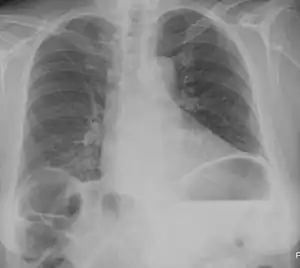

Chilaiditi syndrome is a rare condition when pain occurs due to transposition of a loop of large intestine (usually transverse colon) in between the diaphragm and the liver, visible on plain abdominal X-ray or chest X-ray.[1]

| Chest X-ray showing obvious Chilaiditi's sign, or presence of gas in the right colic angle between the liver and right hemidiaphragm. | |

Normally this causes no symptoms, and this is called Chilaiditi's sign. The sign can be permanently present, or sporadically. This anatomical variant is sometimes mistaken for the more serious condition of having air under the diaphragm (pneumoperitoneum) which is usually an indication of bowel perforation, possibly leading to surgical interventions.